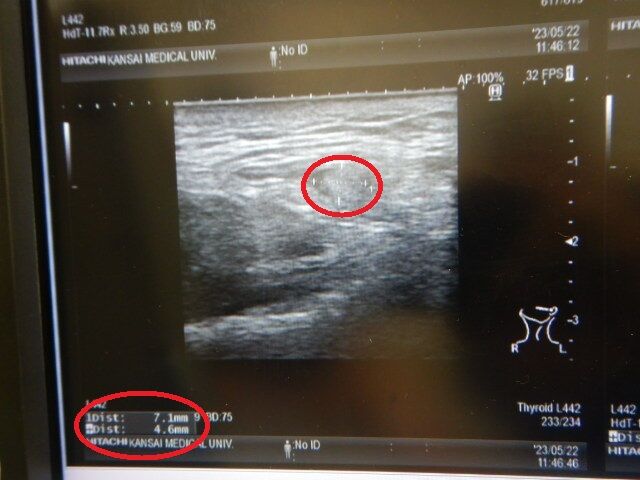

¿¿ÀµÂ¿·ì¾É¤ÈÂñÕÁ£Æ³´É´â

ºòÆü¤Ï¿¿ÀµÂ¿·ì¾É·Ð²á´Ñ»¡¤Î°Ù¤Ë²¿»þ¤â¤ÎÄê´ü·ì±Õ¸¡ºº¤È

Äɲäǡ¢ÂñÕÁ£Æ³´É´â¤Î¥¨¥³¡¼¸¡ºº¡£

¿¿ÀµÂ¿·ì¾É¤ÎÊý¤ÏÆÃ¤ËÌäÂê̵¤¯

¥Ø¥Þ¥È¥¯¥ê¥Ã¥È¤Î¿ôÃͤâ°ÂÄꤷ¤ª¤ê

ÅêÌô¤Ç¡¢·ì±Õ¤â¥µ¥é¥µ¥é¤Ë¤Ê¤Ã¤Æ¤¤¤ë¤Î¤Ç

ÀÖ·ìµå¤Î¿ôÃͤϾ¯¤·Â¿¤¤¤Î¤Ç¤¹¤¬

Á´Á³ÌäÂê¤Ï¤¢¤ê¤Þ¤»¤ó¤Ç¤·¤¿¤¬

¤³¤Î½ê¾¯¤·Ä´»Ò¤Ë¾è¤Ã¤Æ¤¤¤¿¤»¤¤¤Ç

·ìÅüÃͤÈA1c¤¬¾¯¤·¹â¤¯¤Ê¤Ã¤¿¤ï¡Ä

¤Ç¤âÇ¢»ÀÃͤÏÊ¿¶Ñ¤Ê¤Î¤Ç¤Þ¤¡Îɤ¤¤«¤Ê¤¡¡Ä

¤Ç¡¢µ¤¤Ë¤Ê¤ëÂñÕÁ£¤Î²¿¼Ô¤«¤¬¡¢¤³¤Î°ì¥ö·î¤Ç

Ìó1ÐÄøÀ®Ä¹¤·¤Æ¤ª¤ê¡¢ÄɲäÇ6·î1Æü¤Ë

MRI¸¡ºº¤ò¼õ¤±¤ë»ö¤Ë¤Ê¤Ã¤Æ»ÅÉñ¤Ã¤¿¡Ä

¸µ¡¹¤Î·×²è¤Ç¤Ï7·î¤ËMRI¸¡ºº¤À¤Ã¤¿¤Î¤Ç¤¹¤¬

µÞ¤¤¤Ç¸¡ºº¤ò¤¹¤ë»ö¤Ë¤Ê¤ê¡¢6·î1Æü19:30¤ÎͽÌó¤Ë¤Ê¤ê

ÍâÆü¿Ç»¡¤ò¼õ¤±¤ë»ö¤Ë¤Ê¤Ã¤¿¡Ä¤Þ¤Àº£¤Î½ê¤³¤¤¤Ä¤¬²¿¼Ô¤Ê¤Î¤«¤Ï

ʬ¤«¤Ã¤Æ¤Ê¤¤¤Î¤Ç¤¹¤¬¡¢¤½¤ó¤Ê¤ËµÞ¤òÍפ¹¤ëʪ¤Ç¤â̵¤µ¤½¤¦¤Ê´¶¤¸¤Ç¤¹¤¬

¥ê¥ó¥ÑÀá¤â¤«¤Ê¤ê¼ð¤ì¤Æ¤¤¤ë¤·¡¢¤´ÈÓ¤ò¿©¤Ù¤ë°ì¸ýÌܤÎÄˤߤ¬

¥Õ¥¡¡¼¥¹¥È²¿¤È¤«¸À¤¦¤è¤¯¤¢¤ë¾É¾õ¤é¤·¤¤¡Ä¡£